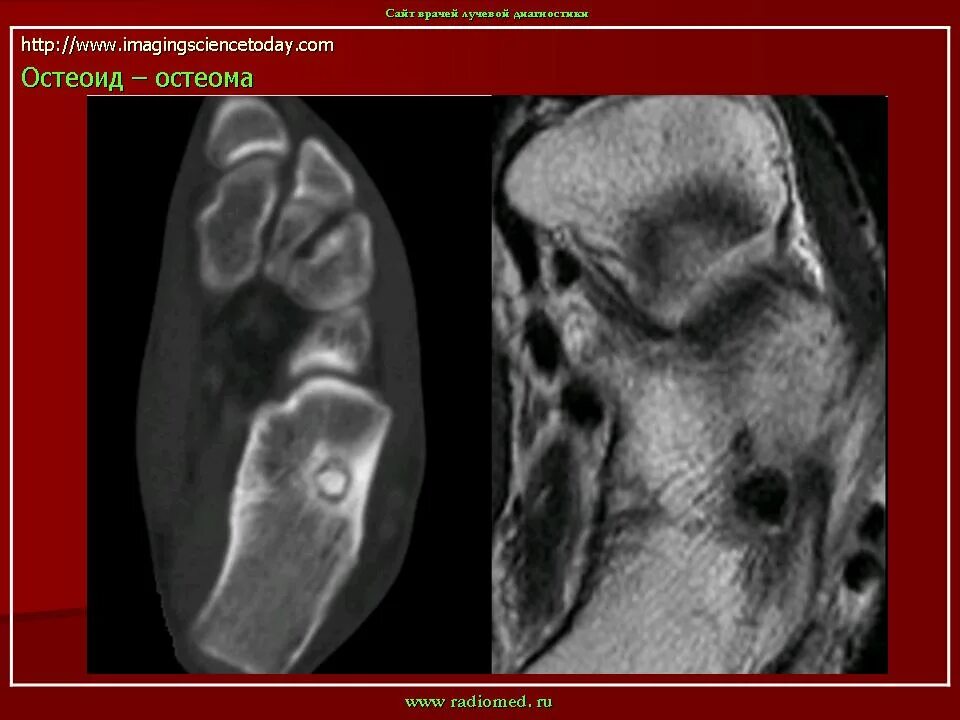

Остеома мрт